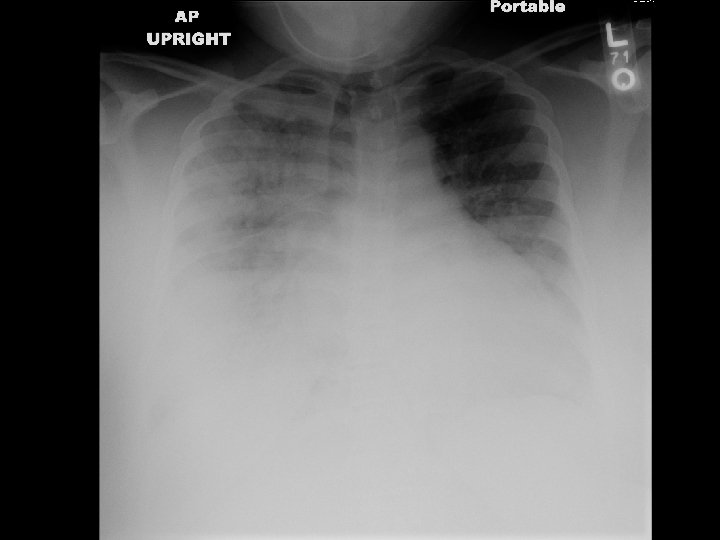

27 year old woman with dyspnea • 4 days s/p C section • Gradual increase in dyspnea over 24 hours with fever of 101 • Evaluation – Crackles R > L – No peripheral edema – Hypoxia (7. 25/67/41 on 40% VM) – Normal Echo

• Diffuse bilateral infiltrates – Patchy, confluent – Alveolar, ground ‐ glass • In contrast to CHF, no prominence of. . – Cardiomegaly – Pleural effusion – Widened vascular pedicle

ARDS: Chest Radiograph Criteria • Radiographic findings not attributable to: – Chronic changes – Atelectasis – Mass – Pleural effusion